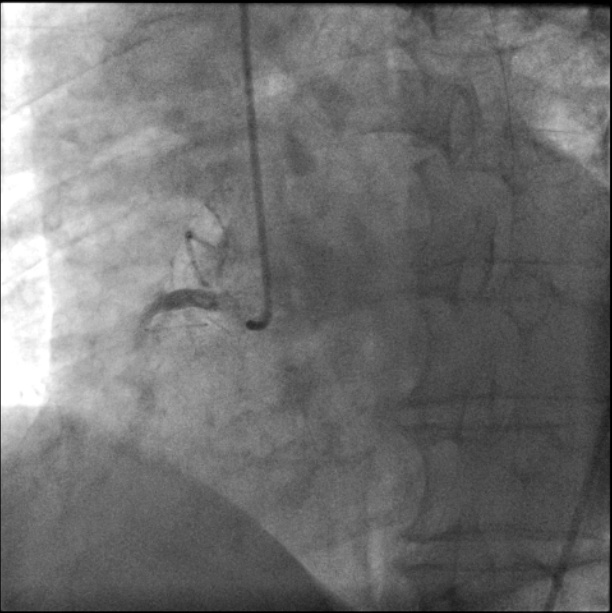

经验丰富的潘慧超主任快速地完成了冠状动脉造影,结果是右冠状动脉完全闭塞伴大量血栓——就是这些血栓堵住了关键的血管,导致了这次严重的急性心肌梗死发生!造影结果也证实了邱主任的判断。

(造影所示右冠状动脉近段闭塞,血栓远段不显影)